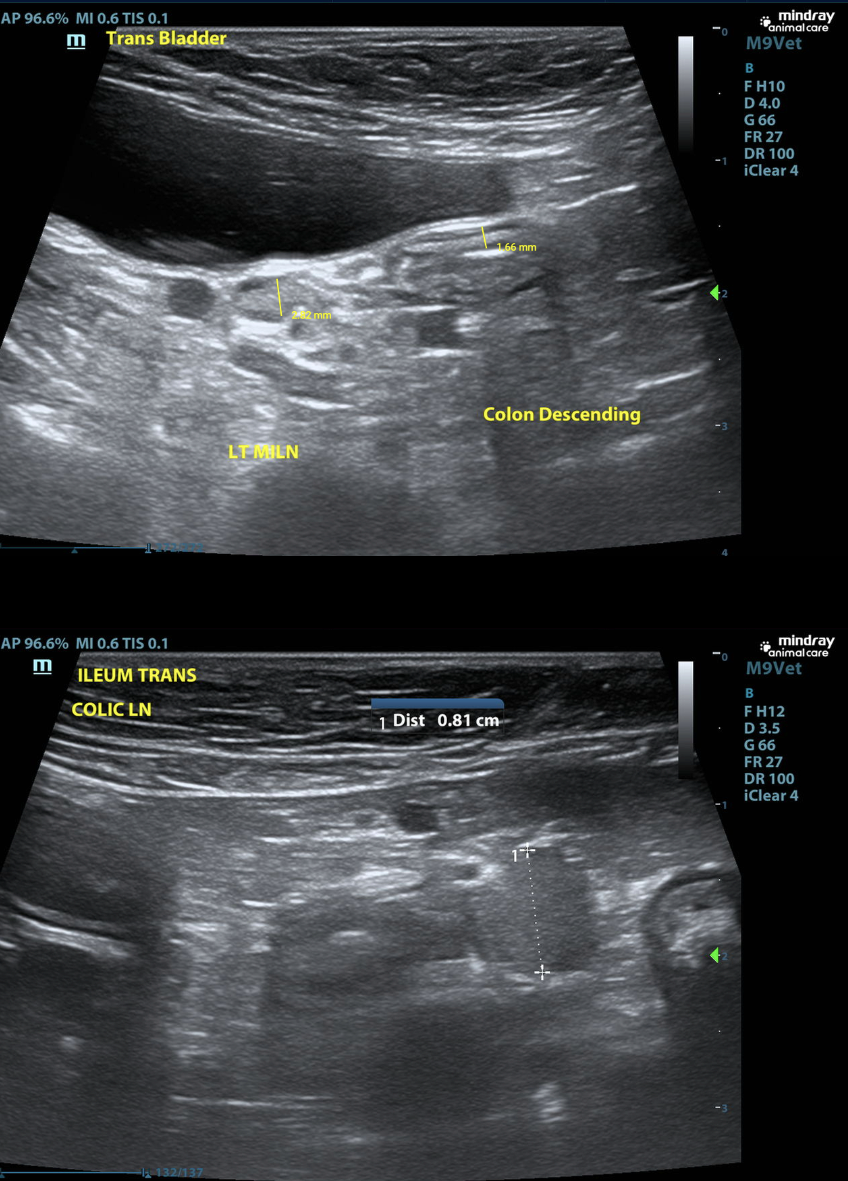

When facing a challenging gastrointestinal case, the power of collaboration cannot be overstated. In this recent case, a 1-year and 7-month-old spayed female Mini Dachshund presented at an emergency clinic with significant gastric distention, regurgitation, and concerns about a possible gastrointestinal obstruction.

The patient had undergone an initial ultrasound exam the previous day, which revealed an ileal foreign body prompting a STAT multi-modality (ultrasound and radiograph) review by the SVS Imaging team. By leveraging the expertise of both a SVS Imaging radiologist and internist, we were able to provide a detailed and actionable care plan.